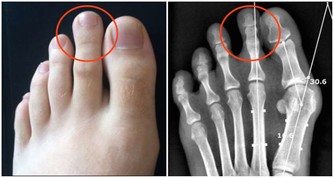

久之這些重金屬就會在腎小管內聚集,嚴重時甚至會引起腎小管的壞死。

其實,他最後的解釋純屬多餘,作為醫生,我知道這重金屬進入人體後會聚集在哪裡,對人體有什麼危害。

我們吃下去之後,這些重金屬就會沉積在我們的腎小管內,久而久之,就會傷及我們的腎臟。